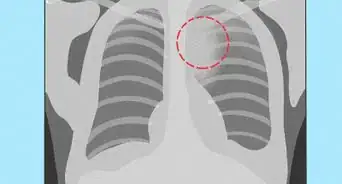

3Put the films in the correct order. Numbers will be printed on the CT films. The CT scan cuts your body into cross-sections which are like very thin slices of bread.[4] As you look at the images in order, you will notice a normal and natural flow. Any sudden breaks can suggest disease or an abnormality.

- When you look at the special X-rays in order, it is like watching a slow-motion film of the structures and organs inside of you and how they relate to each other. If you were looking at a CT of your chest, you would see how your large blood vessels and the bronchi (the tubes through which air flows in and out of your lungs) weave through your uniform lung tissue. Lung cancer would create a noticeable disruption in this pattern.